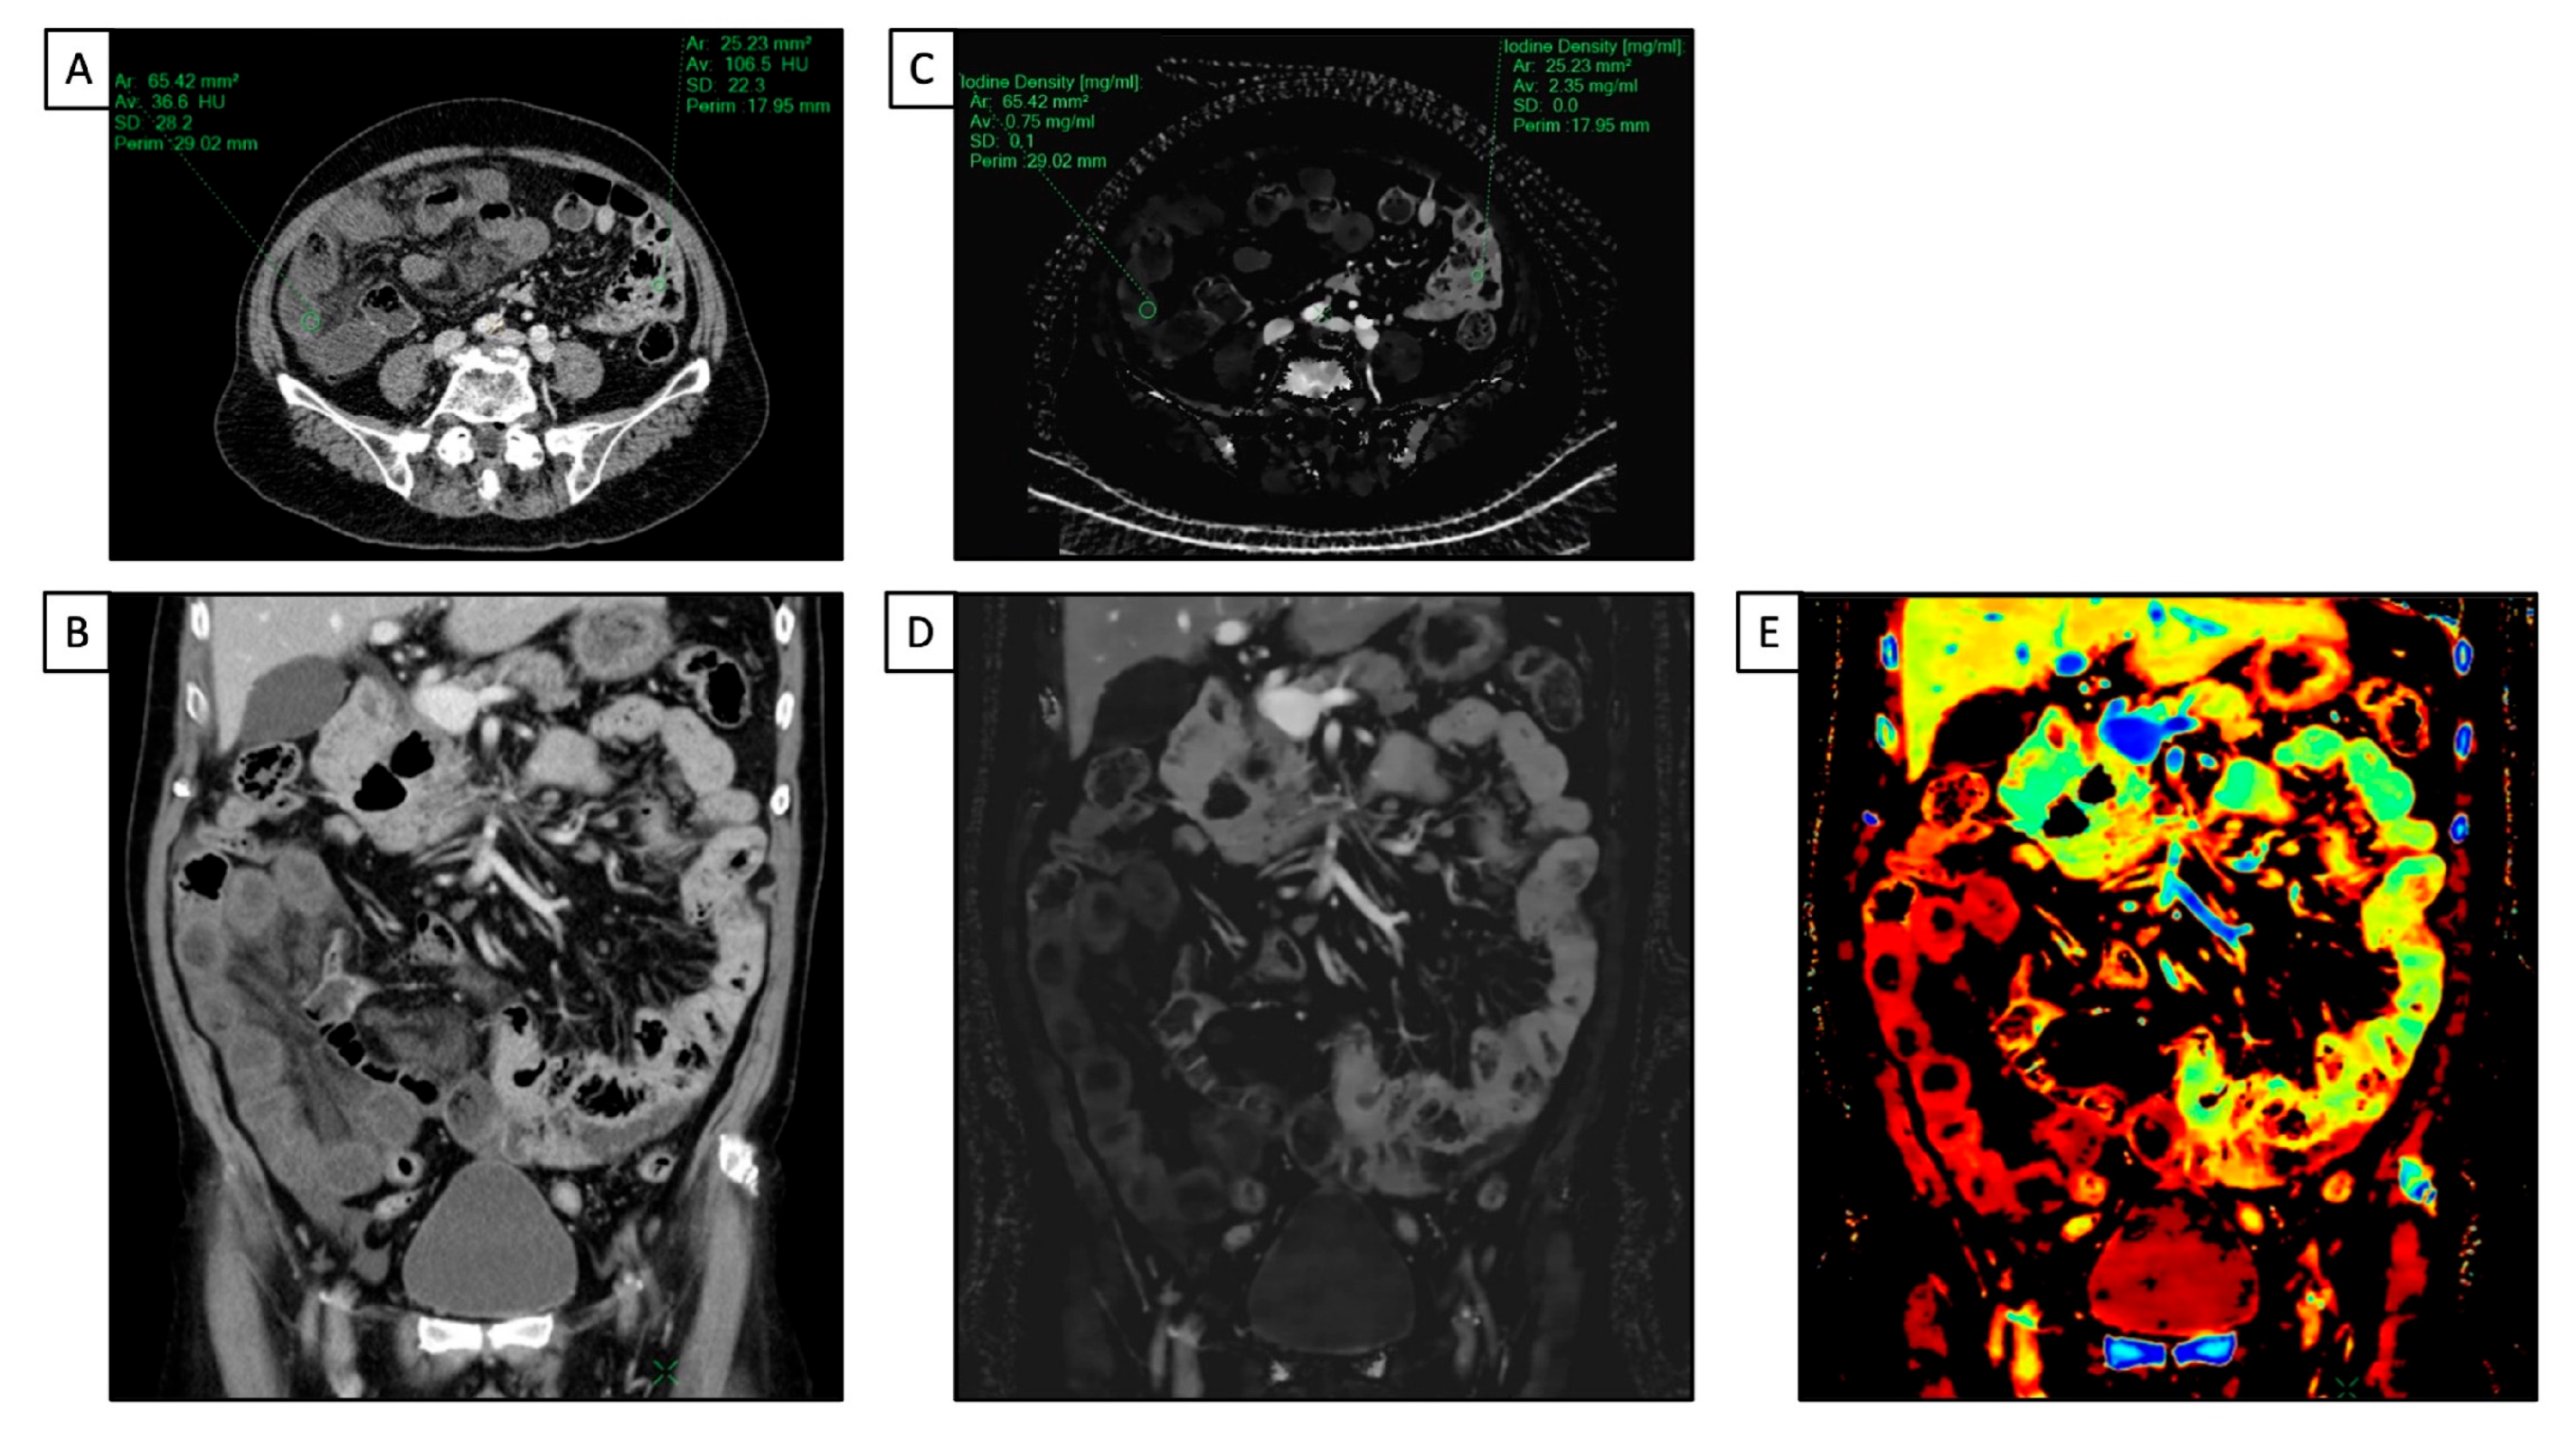

DECT has proven to have many applications, including in the evaluation of gastrointestinal tract diseases. In emergency settings, CECT is typically the preferred imaging tool when acute bowel ischemia is suspected to assess a decreased or lack of bowel parietal enhancement. However, detecting these findings is not always straightforward, especially in the case of early ischemia [42]. DECT can improve confidence in diagnosing bowel ischemia due to its capability in enabling a quantitative measure of wall enhancement via iodine mapping. In addition, a low-keV VMI can highlight the attenuation differences between perfused and non-perfused walls [43,44] (Figure 3).

Figure 3.

A 49 y-o male with known Crohn’s disease, diffuse abdominal pain, and suspected relapse of disease underwent abdominal CT. (A) Conventional CT images on the coronal plane acquired after intravenous contrast media injection show a poor layered enhancement appearance of the distal ileum; (B) iodine map enhances iodine’s uptake by the mucosa layer, and the hypoattenuating appearance of the submucosa one, consistent with edema; (C) the Z-effective map allows us to define the pattern of enhancement due to the atomic number of iodine.

Even if MRI is considered the gold standard in evaluating small intestine inflammatory bowel diseases [Maaser2019], DECT has proven to have high diagnostic accuracy in assessing inflammation activity and severity in those with Crohn’s disease [49,50,51] (Figure 4).

Figure 4.

A 66 y-o male with diffuse abdominal pain underwent abdominal CT with a final diagnosis of distal ileum bowel ischemia. (A,C) Axial and coronal conventional CT images acquired after intravenous contrast media injection show a slight difference in attenuation value (HU) of the small bowel walls, with reduced enhancement in the distal ileum and regular enhancement in jejunum and proximal ileum; (B,D) iodine maps clearly show the difference in iodine uptake between the normal walls of the jejunum and proximal ileum and the poor iodine uptake of the distal tract of the ileum; (E) the Z-effective map allows us to better and more simply define the different enhancement in terms of colors between healthy and ischemic bowels due to the atomic number of iodine.